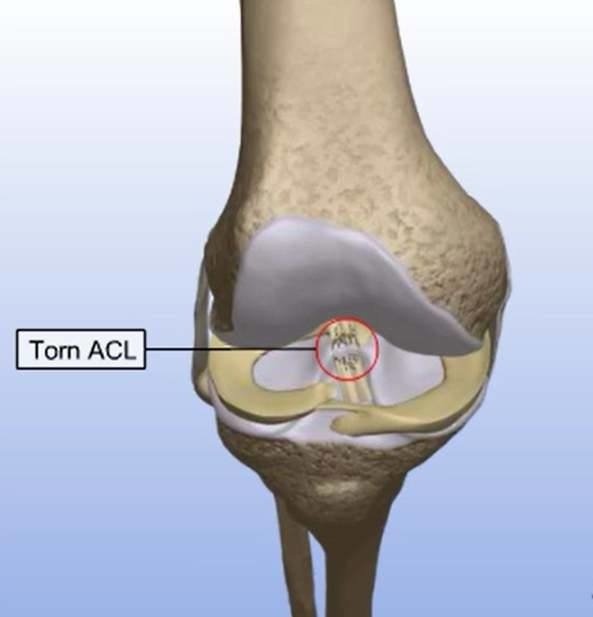

膝前十字靱帯 (ACL)損傷とは 膝には、関節の動きをコントロールする4本の靱帯があります。 前十字靭帯はそのうちの一つで、膝が伸びすぎないように抑えたり、膝の前ずれや捻りの方向への動きを制御をしています。 ジャンプの着地や急な方向転換、相手Acl術後の固有感覚の回復過程について,術後6か月で 正常な機能に戻るという報告がある4).今回の総軌跡長の 変化では,男女とも経時的に有意な減少を認め,術後6か 月以降に安定する傾向を示し,同様の結果が得られたと考 acl再建術後患者のスポーツ復帰において、テーピング、装具または両方の併用、いずれが推奨されるか? 確認 7 acl再建術後のスポーツ復帰基準において筋力、関節可動域、動作いずれが判断材料として推奨されるか? 確認 8